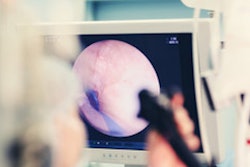

Olympus and Hitachi have signed a five-year contract to continue their alliance in the development of endoscopic ultrasound systems (EUS).

Hitachi and Olympus have been working together since the 1980s on endoscopic ultrasound scanners, with Hitachi supplying ultrasound technology to work with Olympus endoscopes. The deal announced this week will continue that alliance.